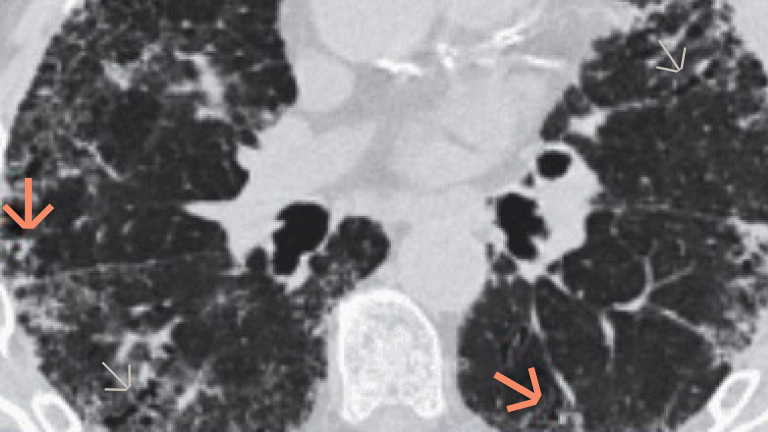

Obrazowanie włóknienia płuc metodą HRCT